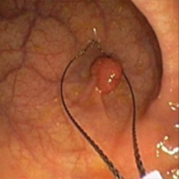

용종제거술